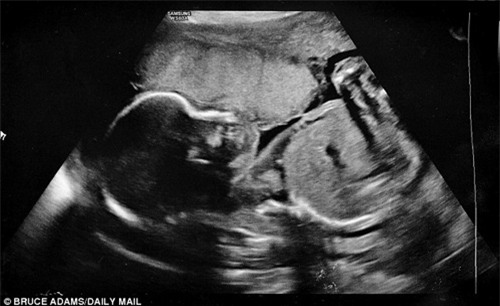

Kể lại về lần mang thai đứa con thứ 2 của mình, chị Louise Adams (sinh sống tại Staffordshire, Anh) cho biết chị bất ngờ vỡ ối non khi mới mang bầu được 22 tuần. Khi đó, chị được bác sĩ thông báo em bé chỉ có 5% cơ hội sống sót.

Chị Adams bị vỡ ối non khi mang thai mới 22 tuần.

Em bé may mắn sống sót khi chị nỗ lực uống tới 4 lít nước mỗi ngày.